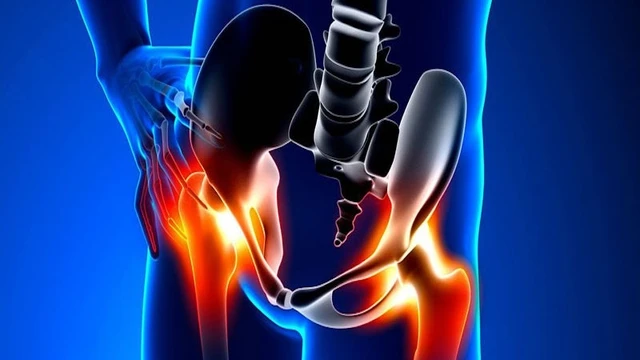

Hoại tử khớp háng đang ngày càng trở nên phổ biến và có xu hướng ảnh hưởng đến những người trẻ tuổi. Đây là một bệnh lý nghiêm trọng với khả năng gây tàn tật cho người mắc, tuy nhiên lại phát triển âm thầm và dễ bị nhầm lẫn với các bệnh lý khác. Vậy nguyên nhân, triệu chứng và cách chẩn đoán hoại tử khớp háng là gì? Để giải đáp thắc mắc mời bạn đọc cùng tham khảo bài viết dưới đây.